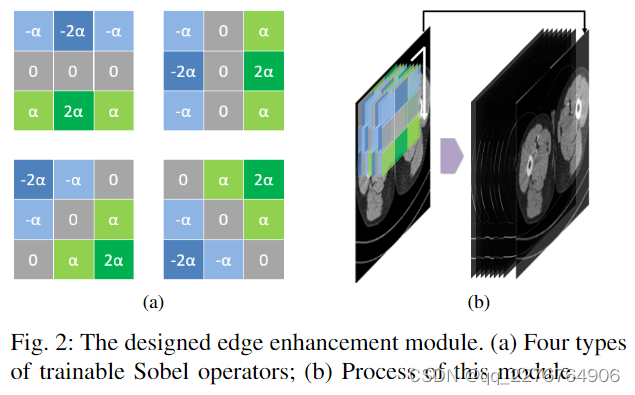

在这个模块中,我们设计了可训练的 Sobel 卷积。 如图2a所示,与传统的定值Sobel算子[25]不同,可训练的Sobel算子中定义了一个可学习的参数α,我们将其称为Sobel因子。 该参数的值可以在训练的优化过程中自适应调整,从而可以提取不同强度的边缘信息。 此外,我们定义了四种类型的算子作为一个组(图2a),包括垂直、水平和对角线方向。 该模块中可以使用多组可训练的 Sobel 算子。

在该模块的流程中(图2b),首先,它使用一定数量(4的倍数)的可训练Sobel算子对输入CT图像进行卷积运算以获得一组用于提取边缘信息的特征图。 然后模块将它们与输入的低剂量CT图像在通道维度上堆叠在一起,得到该模块的最终输出。 该模块的目标是在数据源层面丰富模型的输入信息,强化边缘信息对模型的影响。